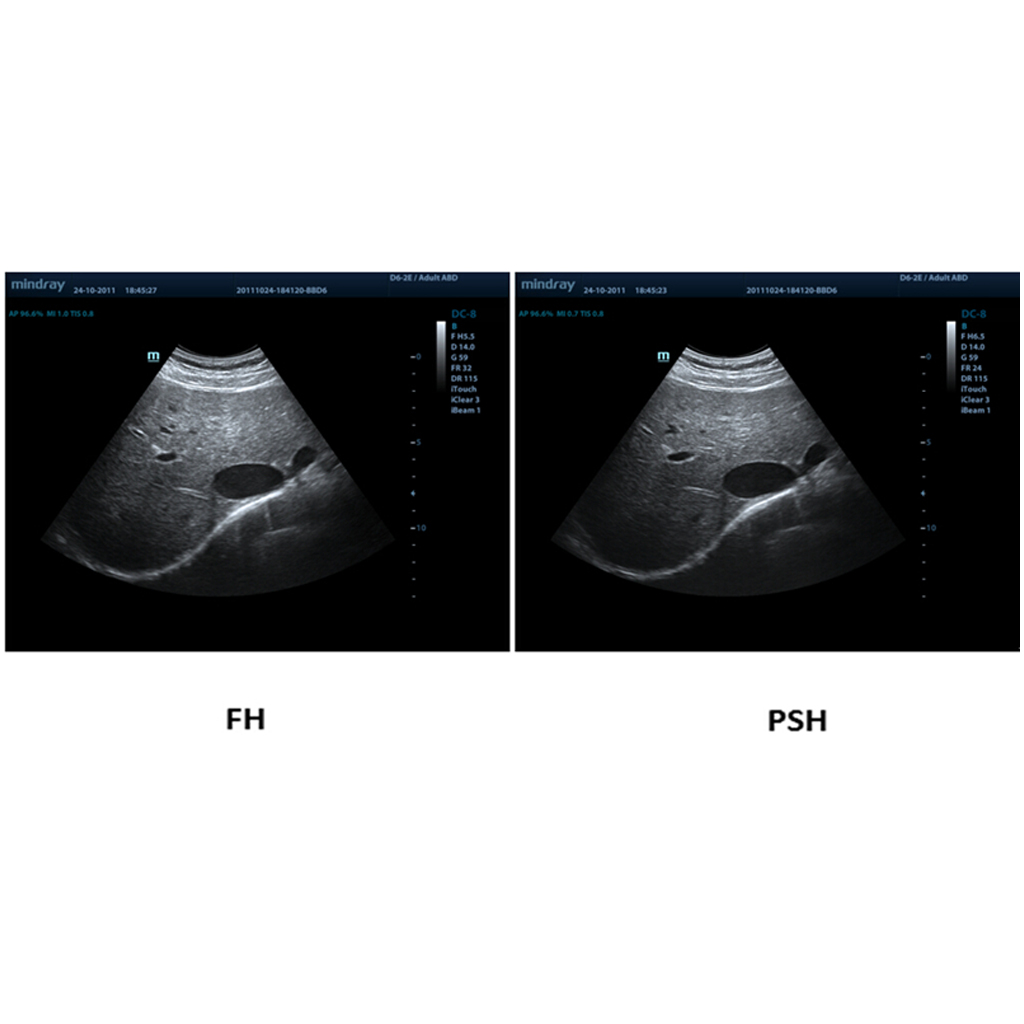

PSH™ (Phase Shift Harmonic Imaging)